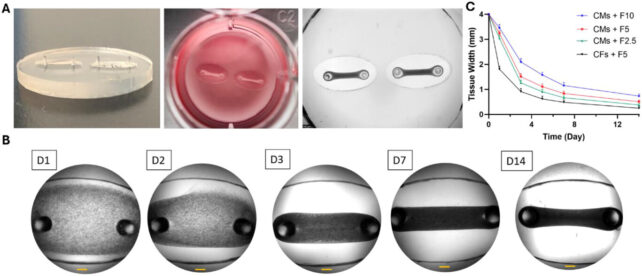

To construct their HOC models, the research team isolated cardiac muscle and connective tissue cells from rat subjects. These cells were subsequently cultured within a hydrogel-rich matrix, enriched with structural proteins and essential nutrients to foster cellular proliferation. This engineered tissue was then carefully positioned onto miniaturized, pliable silicon-based substrates.

The researchers strategically incorporated two distinct sensor types into the HOC architecture. For the assessment of gross contractile forces, the engineered cardiac tissues were suspended between two flexible, elastomeric pillars. The degree to which these pillars deform with each cardiac cycle directly correlates with the overall contractile strength of the tissue construct.

Furthermore, the team embedded pliable, hydrogel-based microsensors directly within the cardiac tissue. The subtle deformations experienced by these microscopic structures, which average approximately 50 micrometers in diameter, serve to capture localized mechanical stresses at the cellular level.

This development represents a significant stride towards replicating pathological processes in vitro, given that cellular forces are instrumental in dictating the behavior of cardiac tissues, encompassing their development, structural adaptation, contractile efficiency, tissue repair mechanisms, and even their susceptibility to malignant transformations.

The initial compound administered was norepinephrine, also known as noradrenaline. This sympathomimetic agent, which stimulates the body’s “fight-or-flight” response, is clinically employed to augment cardiac activity and stabilize blood pressure, particularly in critical situations such as cardiac arrest.

To induce the inverse effect and diminish contractile activity, the researchers subsequently applied blebbistatin, a pharmacological agent that inhibits muscle contraction.

The observed drug responses precisely aligned with theoretical predictions, substantiating the HOC’s capacity to accurately forecast the impact of common pharmacologic agents on myocardial force generation and cardiac rhythm.